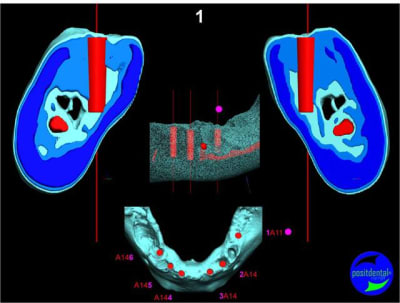

Extraction, pose d’implants Ankylos, pose des piliers Standard définitifs, mise en charge immédiate bi-maxillaire en une chirurgie.

Maxillaire inferieur – extraction 35, 34, 44, 45, 6 implants MCI, comblement osseux, bridge provisoire sans fausse gencive avec renfort métallique.

3D

Préopératoire

uniquement le scan pré-op

en attendant la pano voici les coupes de la S.I.A.O.